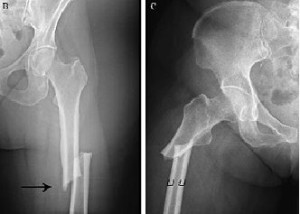

Beneficios y riesgos a largo plazo de los fármacos para prevención de fracturas

25 abril 2019